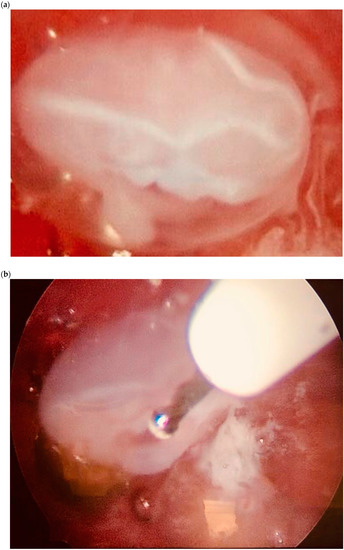

| Case 1 | Asymptomatic | 12 + 1 | 97,388 | GS 78 × 60 mm; with embryo | Radical surgical treatment (LPS hysterectomy + bilateral salpingectomy + uterine arterial embolization + bilateral ureteral stent placement) | Complete resolution |

| Case 2 | Asymptomatic | 6 + 6 | 10,862 | GS 20 × 19 mm; with embryo | Hys: 1st step: CP resection by twizzle; IC Foley catheter 2nd step: vessels electrocoagulation by bipolar twizzle | Reoperation (hys) due to tissue residues and cervical laceration Complete resolution |

| Case 3 | Asymptomatic | 5 | 9747 | GS 20 × 22 mm; no embryo | MTX IM 50 mg/m2 of body surface + Hys | Complete resolution Currently pregnant (PMA Homologous) |

| Case 4 | Brownish vaginal discharge | 6 + 6 | 55,951 | GS 30 × 10 mm; no embryo | Hys | Complete resolution |

| Case 5 | Vaginal bleeding | 9 | 1331 | GS 4.7 × 5 mm; no embryo | Mifepristone 600 mg orally + Misoprostol 400 mcg + MTX IM 50 mg/m2 of body surface | Complete resolution |

| Case 6 | Vaginal bleeding | 6 | 4274 | GS 5.4 × 5 mm with embryo | MTX IM 50 mg/m2 of body surface + Hys: CP resection by twizzle | Complete resolution |